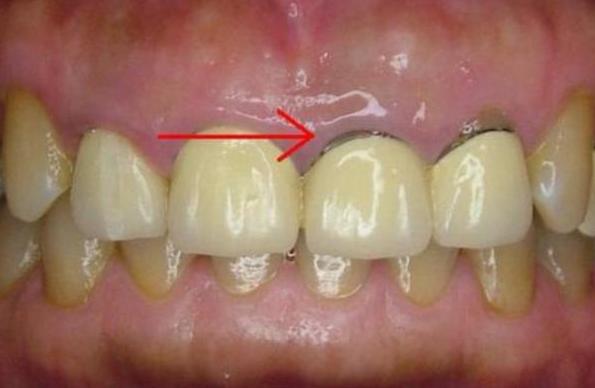

2、阻止牙龈萎缩

烤瓷修复牙冠边缘与牙龈密合程度是判断烤瓷牙是否成功最重要的指标,密合不佳则会使细菌进行牙冠内,导致牙齿发言、牙龈萎缩、牙龈发黑等。

4、冠体材料更换

当长期佩戴烤瓷牙出现牙龈黑线,经医生检查确认需要进行冠体更换时,建议根据自身情况,尽可能选择中等价格偏上、对身体无害且组织相容性好的材质,例如选择全瓷或仿生材质,最大限度的避免选材不当造成的烤瓷修复失败。